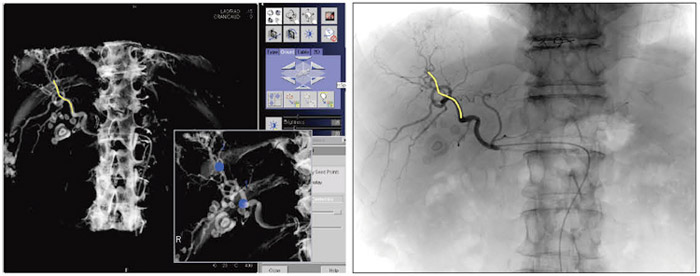

Clinical Applications Translumbar Type II Endoleak ...

Clinical applications Translumbar type II endoleak embolization using real-time needle guidance and fluoroscopy overlay on pre-treatment CTA guidance in translumbar embolization of type II endoleaks. Currently, this is our preferred ... View Document